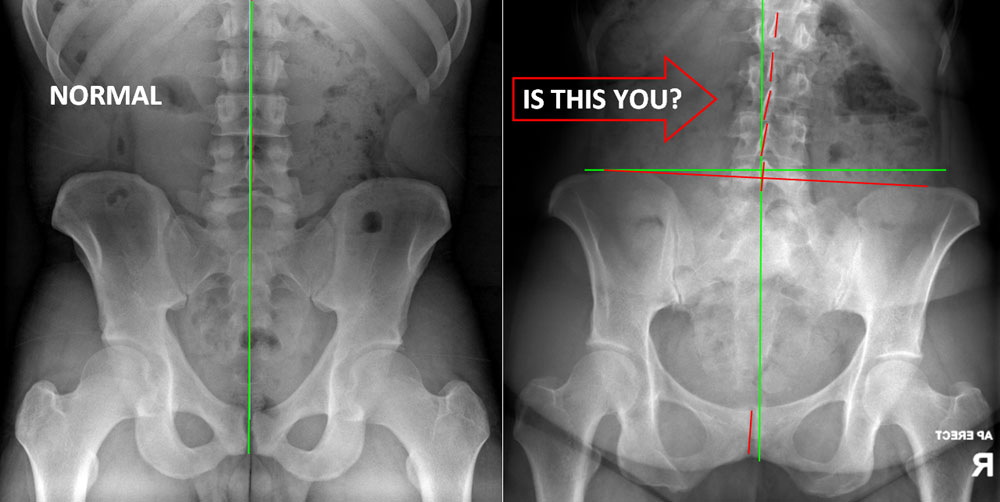

2. Digital X-ray Analysis - Bones and Joints

3. Digital Postural Analysis - Postural Distortions

(It includes a thorough examination of your spine and pelvis and tests your mobility, muscle function and reflexes, supported by digital postural analysis and x-rays (when clinically indicated). We aim to correct areas of dysfunction that are causing your symptoms, not just the symptoms themselves.)